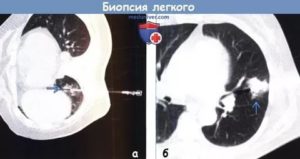

Для точного определения положения иглы относительно предназначенного для исследования области биопсия выполняется под контролем методов медицинской визуализации – рентген или УЗИ. Во время исследования необходимо задерживать дыхание и удерживаться от кашля.

- Чрескожная трансторакальная биопсия. Выполняется длинной толстой иглой путем прокола грудной стенки под ультразвуковым или рентгенологическим контролем.

чрескожная пункционная биопсия

Игла продвигается под контролем УЗИ, флюороскопии, или КТ. При этом главная задача пациента – находиться неподвижно в течение 20-30 минут, не кашлять. Несколько раз потребуется задержка дыхания. Положение – сидя или лежа (при КТ контроле).